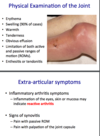

suppurative joint

phys exam & extra-articular sx

erythema/swelling/ tenderness etc - v obvious

sx of infl arthritis, synovitis - usually no real extra-articular sx!